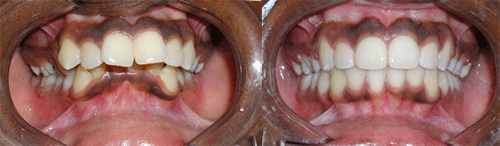

Protruded teeth (bucked teeth) happen when either the upper jaw is too far forward, the lower jaw is too far back, or a combination of both. Expert analysis allows us to determine the cause of the protrusion, and the most effective treatment plan.

With this type of bite, the front teeth are very protuded, and makes these delicate teeth highly prone to trauma, injury, and even premature tooth loss.

We have a number of different options and appliance types for correcting protruded teeth. The photos below illustrate protruded teeth, and the corrections in our patients.